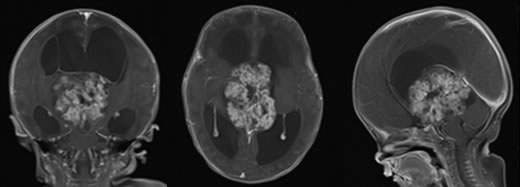

头增强MRI检查结果:第三脑室占位性病变,脑积水。

入院诊断:颅内生殖细胞肿瘤(未成熟/恶性畸胎瘤?内胚窦癌/含内胚窦成分的混合生殖细胞肿瘤?)、梗阻性脑积水。